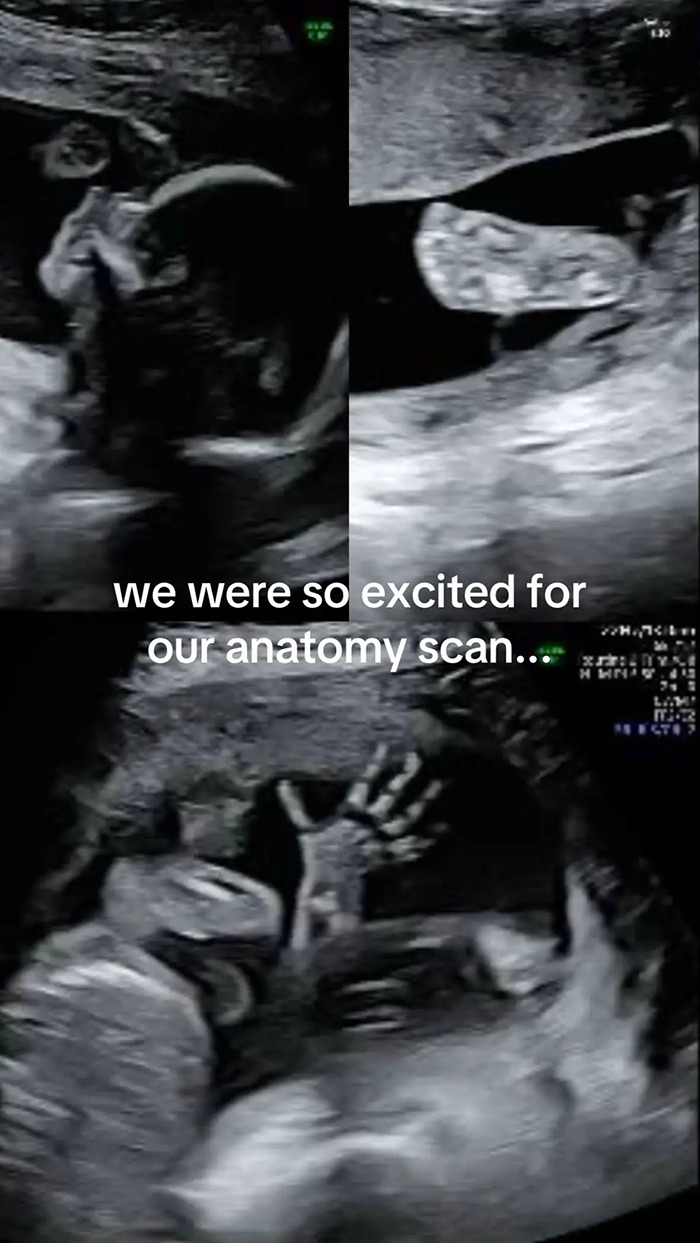

Inês Egner, an influencer and soon-to-be mother from Portugal, couldn’t believe her eyes when her 20-week anatomy scan revealed something unexpected, and hilarious.

Instead of her baby, the machine showed what appeared to be the face of her dog, Goulash, staring back at her.

The video, uploaded to TikTok on October 9, 2025, has now been viewed over 3 million times, with commenters both laughing and agreeing that the resemblance between her unborn son and her five-year-old dog was impossible to unsee.

“We were so excited for our anatomy scan,” Egner wrote across the first slide of her post. “Only to get our photos back and realise our son looks remarkably like our dog!”

Speaking to her followers and media outlets, Egner recounted how she first noticed the likeness while looking through the photos with her best friend and husband after the scan.

“We were skimming through them together, the three of us, as you do, admiring the little hands, the little nose… until we came across that picture and my friend goes, ‘Wait, doesn’t the baby look just like Goulash?’” she told People Magazine.

“Hard to unsee the uncanny similarity after that,” she added. “My husband and I instantly started laughing because we could see it too.”

As for what created the strange, dog-like image. Egner explained to her viewers that it was most likely the result of a weird angle.

“They were checking from the angle of his chin, checking up his nostrils and his eyes,” she said.